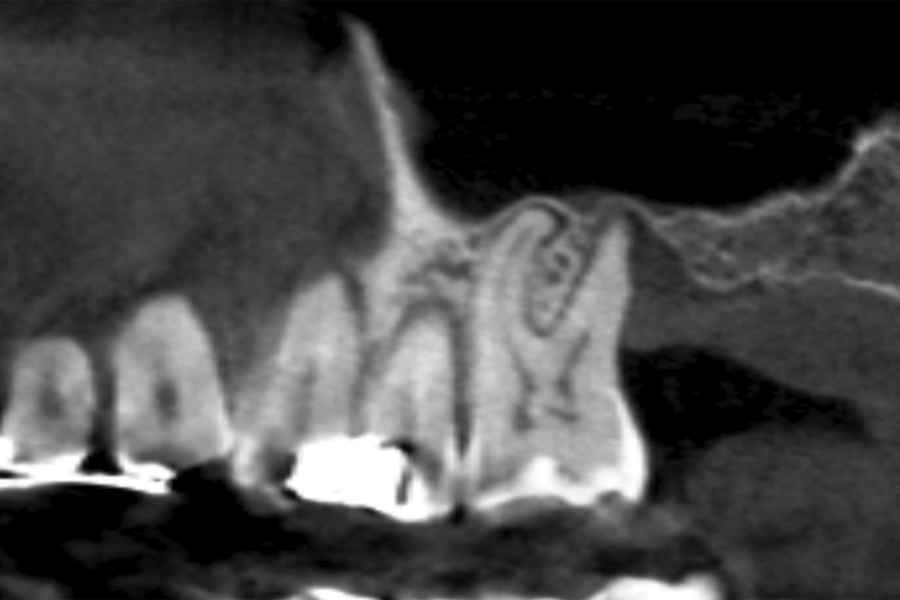

In all cases, a diagnosis was made based on study models, intraoral examination of the patient and performing a Cone-beam analysed using the specific BTI-Scan 3 software (Biotechnology Institute, Vitoria, Alava, Spain).

Patients attend subsequent check-ups performing a control Cone-Beam after 5 months (before loading the implant) and after one year of the load, performing a new measurement in these images to analyse the bone gain and the maintenance of the same. In these check-ups, data are collected on prosthetic complications or crestal bone loss in these patients, as well as possible failures.

The mean height of the residual bone volume was 3.1 mm (+/- 0.3 mm with a range of 3-4 mm). In all cases, transcrestal sinus elevation was performed, with particulate autologous bone obtained from milling the neo alveolus generation zone for implant insertion, being the average of this elevation above the apex of the implant of 2.8 mm (+/- 0.99 range 1.9 -5 mm). In the CT control scan after one year of inserting the studied implants, the bone gain achieved was maintained, no decrease in the volume gained was observed, only three cases showed a decrease of between 0.4 and 0.5 mm of the initial volume at the end (Table).

Figures 2-19 show one of the cases included in the study.